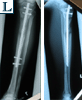

▪ Bilateral tibial

lengthening

▪ Ilizarov with

lengthening-over-nail

technique

▪ Lengthening at 1mm / day

▪ Tibial Intra-medullary nail distal locking

▪ Removal of Ilizarov frame and intra-medullary tibial nailing